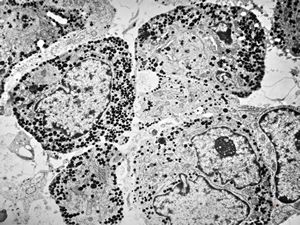

M, 14y. | pheochromocytoma

M, 38y. | pheochromocytoma